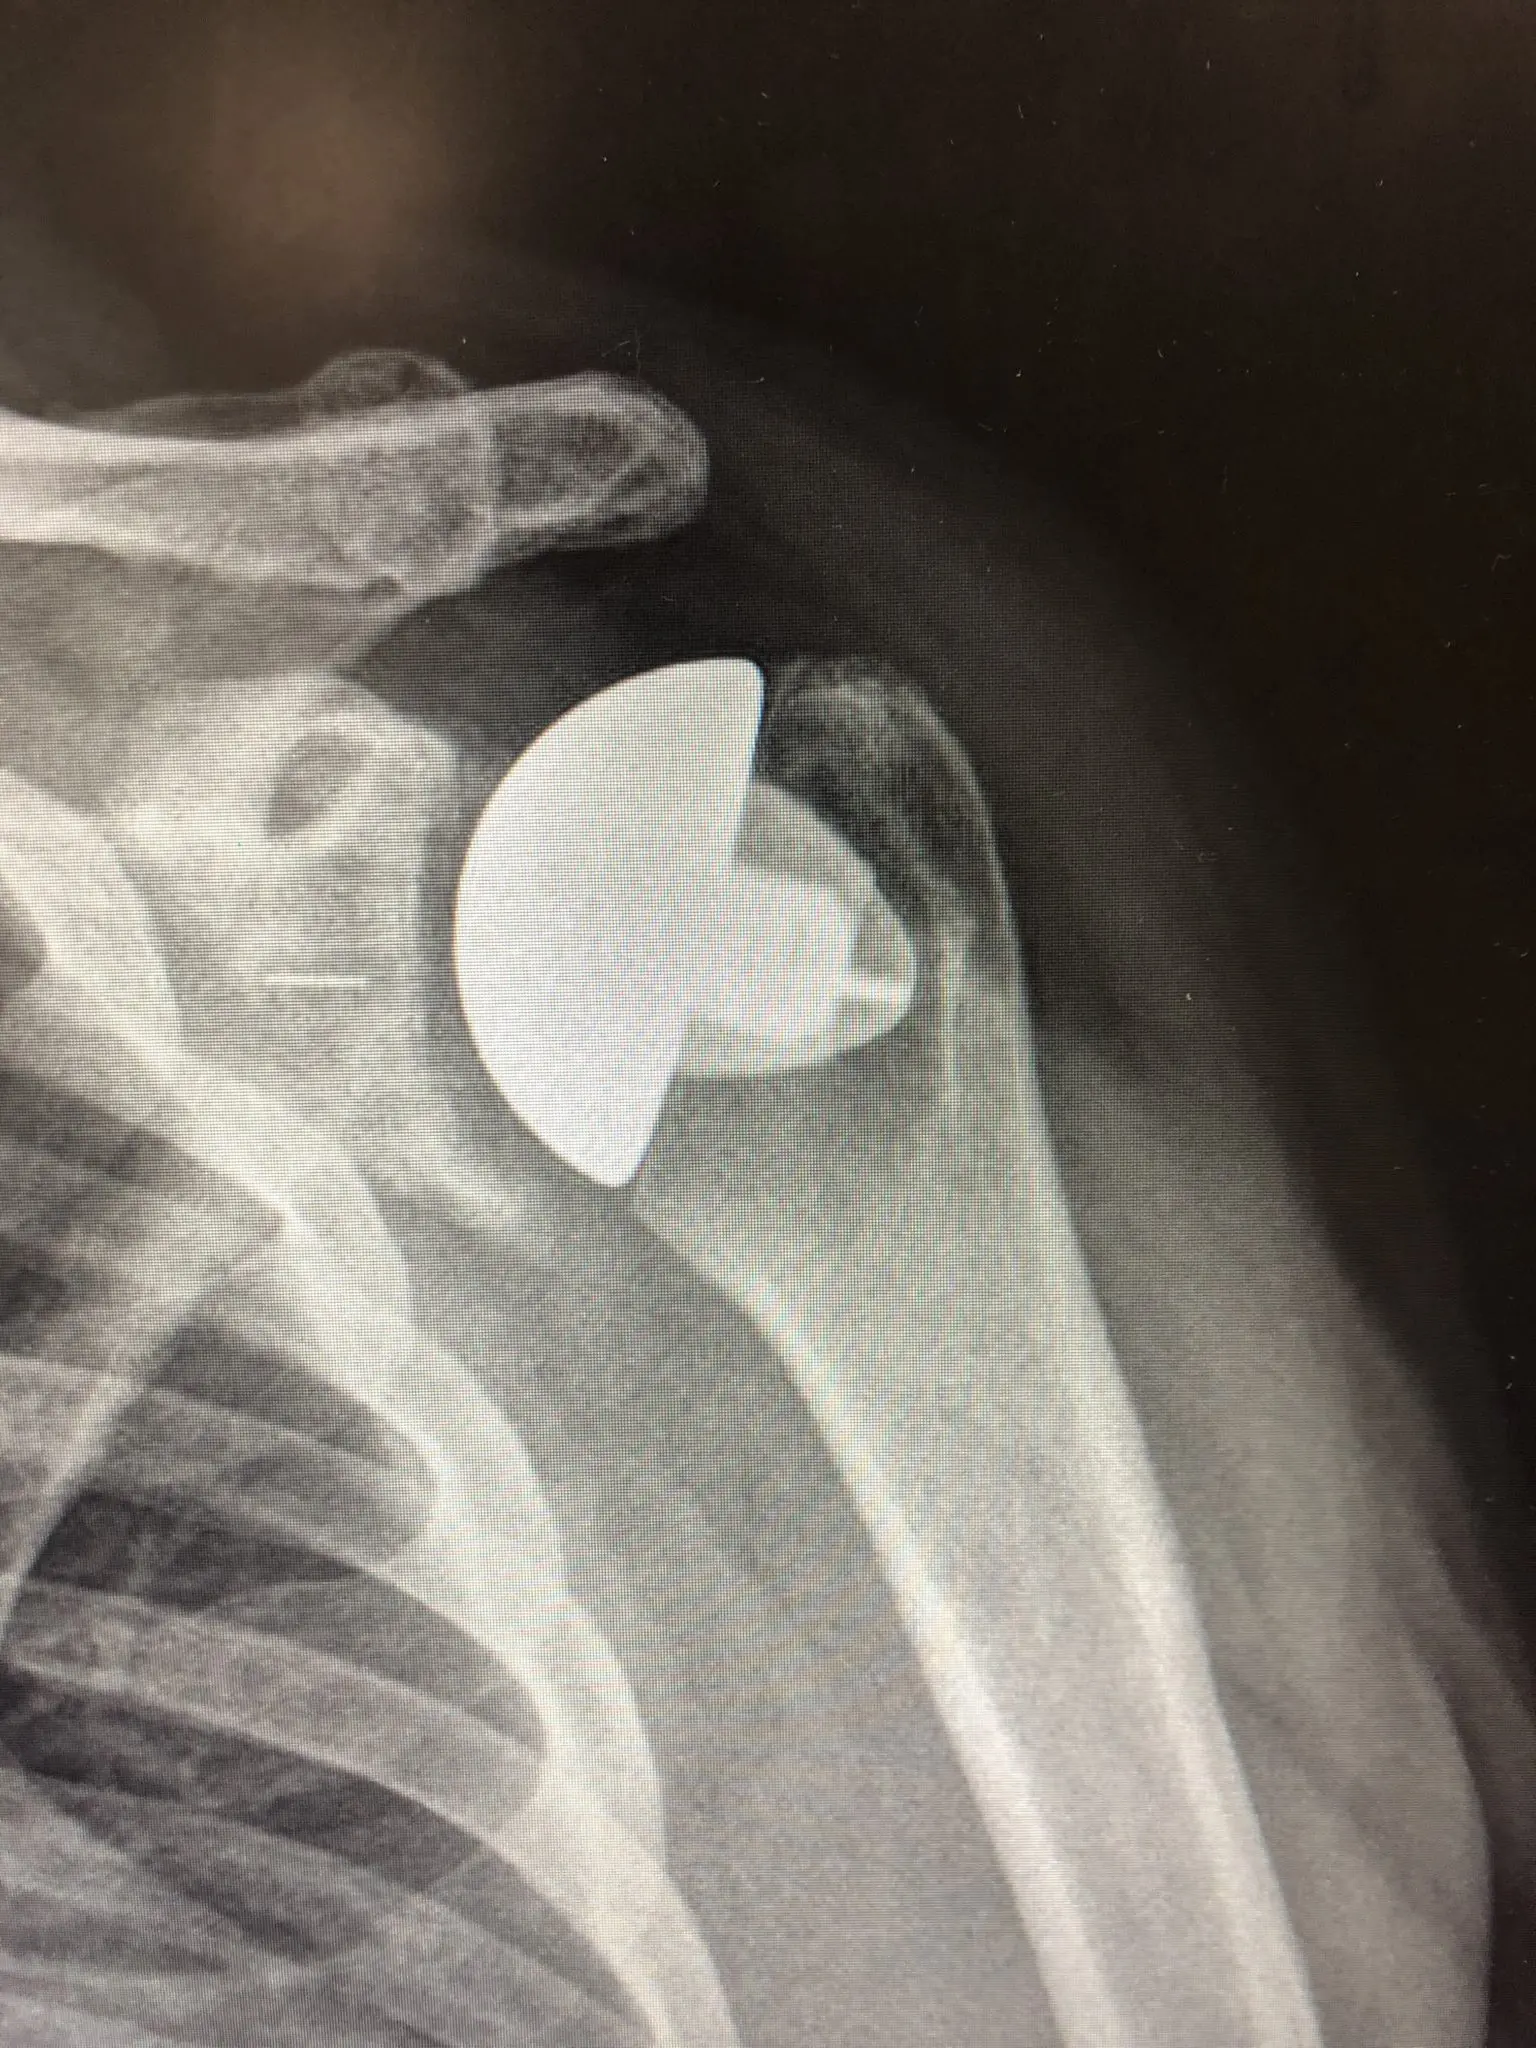

Zdjęcie RTG - endoprotezoplastyka barku

Jeśli zmiany zwyrodnieniowe są bardziej zaawansowane, szanse na wyleczenie i powrót do aktywności daje endoprotezoplastyka stawu barkowego, czyli zastąpienie zużytych powierzchni stawowych endoprotezą. Operacja wymiany stawu trwa około dwóch godzin. Po zabiegu kończyna unieruchamiana jest w ortezie na 4-6 tygodnie, aby przecięte ścięgna miały czas na gojenie. W tym okresie wdraża się ćwiczenia barku pod kontrolą fizjoterapeuty. Powrót do codziennych aktywności i prowadzenia samochodu zajmuje ok. 6 tygodni, do aktywności sportowej 3-6 miesięcy. Całkowita rekonwalescencja trwa do 12 miesięcy.

W ciągu ostatnich 20 lat endoprotezoplastyka barku stała sie standardem w leczeniu zmian zwyrodnieniowych barku na świecie. Obecnie istnieją możliwości rekonstrukcji 3D (trójwymiarowej), pozwalającej na personalizację endoprotezy i jej precyzyjnego dostosowania do anatomii pacjenta, tym samym zmniejsza sie ryzyko wcześnejszego obluzowania oraz innych powikłań.